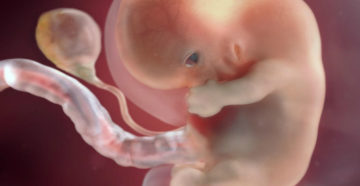

8 неделя беременности. Плод 8 недель Восьмую неделю беременности еще также называют шестой эмбриональной неделей….

8 неделя беременности Наверняка вы уже думали над именем ребенка и не раз гадали, мальчик…

8 неделя беременности: что происходит с малышом и мамой, ощущения, развитие плода Каждая неделя беременности…